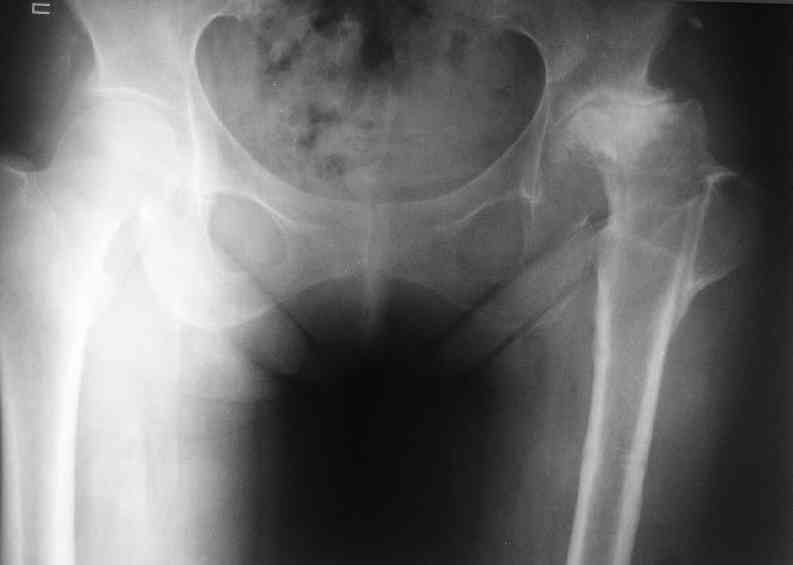

Не такое уж страшное укорочение по снимкам.Вчера прооперирован похожий

случай.Обошлись без релиза и аппаратного низведения. Укорочение было 4

сантиметра.Теперь ножки ровные.